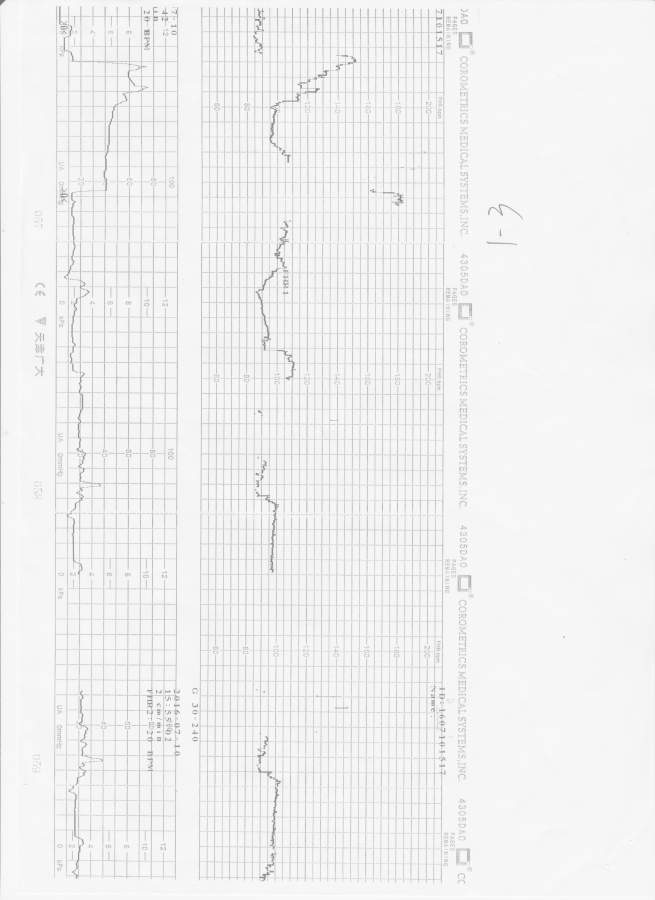

女儿出生重度缺氧,拜请懂得的各位看看什么时候开始胎心不正常

这是一张完整的胎心监护的记录,但是由于一次扫描不开,所以我分成了几段。跪请帮我看看15:50前是不是已经不正常,或者是已经胎儿窘迫了? 胎心监护1-1.jpg 胎心监护1-2.jpg 胎心监护1-3.jpg 胎心监护1-4.jpg |